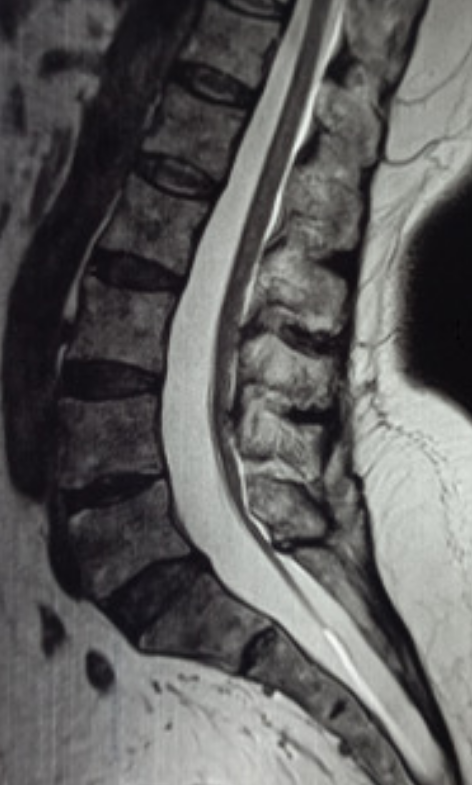

Conus level refers to the lowermost tip of the spinal cord (normally around L1/L2), while filum thickness describes the fibrous strand (filum terminale) extending from it. A thickened filum (>2mm) or a low conus level (below L2/L3) often signals Tethered Cord Syndrome (TCS). It is a clinical neurological disorder caused by abnormal tissue attachments that restrict normal movement of the spinal cord within the spinal canal. This pathological fixation results in chronic traction on the spinal cord, leading to ischemia, metabolic dysfunction, and progressive neurological deterioration. While classically associated with a low-lying conus medullaris or a thickened filum terminale, tethered cord syndrome can occur even when the conus is in a normal position, particularly in adults.

• Obtain lumbosacral MRI (sagittal and axial T1/T2; include whole-spine screening when dysraphism is suspected).

• Conus level

• Identify the tip of the conus (transition from cord to cauda equina).

• Record the vertebral level using reliable landmarks (vertebral bodies and disc spaces).

• Filum thickness

• Measure the filum on axial images where it is best visualized, recording its maximal diameter.

• Assess for fat signal within the filum (T1 bright; fat-sat confirms).

• Look for additional tethering clues that matter clinically and surgically:

• Posterior displacement/taut appearance of the conus and filum

• Low-lying conus is commonly defined as termination below the L2–3 disc space.

• Filum terminale: Thickened filum is commonly defined as >2 mm at the L5/S1 level (most often applied in pediatric imaging; still used broadly as a practical threshold).